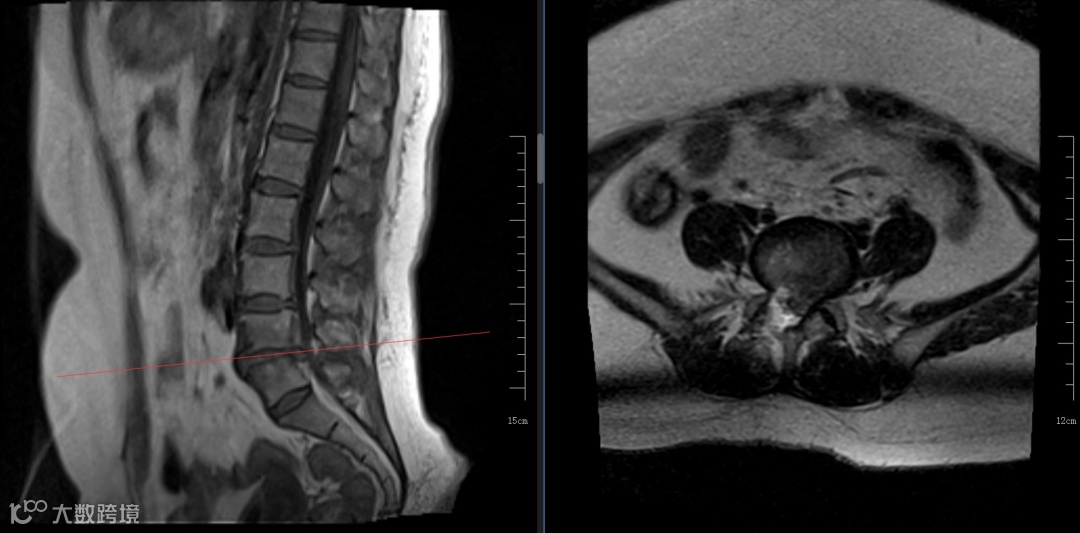

陈大爷术前影像学资料

70岁的陈大爷也遇到了和刘先生同样的情况,1年前无明显诱因出现腰部疼痛不适,自行在家休息后症状缓解,2周前弯腰劳作后出现腰部疼痛伴右臀部及下肢放射痛,持续加重,昼夜难眠遂被送来我院。检查发现患者脊柱、退变、骨质增生伴椎体不稳,多阶段椎间盘变性突出,详细查体后结合磁共振定位腰4/5为责任节段,骨科医师团队在路江鸿主任的带领下经过反复讨论认为,患者高龄,脊柱退变,本次发病为劳累后诱发腰4/5椎间盘急性突出相应神经根受压,开放手术对老人风险较高,决定行侧路椎间孔镜手术对患者较为合理。手术顺利,术后症状立即缓解,老人终于睡上了安稳觉。